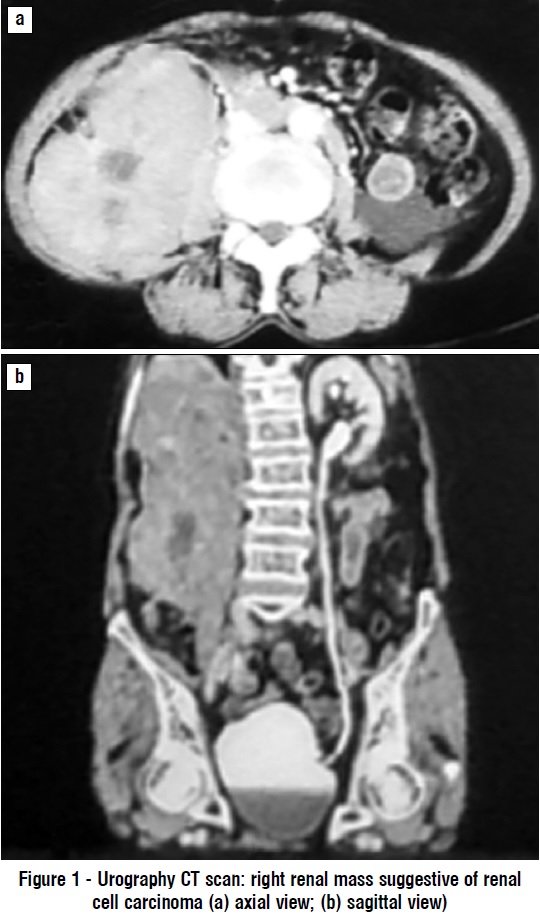

Laboratory examination showed normal complete blood count, blood chemistry, electrolyte levels, and urinalysis. A plain chest X-ray showed an elevated right diaphragm (suggestive of an intra-abdominal process) but found no sign of metastasis. Abdominal ultrasound indicated a right renal mass suggestive of RCC (differential diagnosis: urothelial tumor) with right hydronephrosis and found no metastasis to surrounding organs. Urography CT scan (fig. 1) visualized a right renal tumor suggestive of RCC.

The patient’s abdominal ultrasound showed a right renal mass suggestive of RCC (differential diagnosis: urothelial tumor) with right hydronephrosis. A urography CT scan also showed a right kidney mass suggestive of RCC. Zhao et al and Cheng et al concluded that PRL could be misinterpreted as RCC due to its scarcity; in their research, PRL tumors were described as homogenous masses with lower density, unclear margins, minimal vascularization, and less enhancement with contrast (1,8).